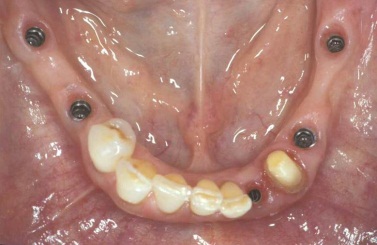

Během let může postupnou ztrátou zubů zůstat v ústech omezený počet zubů, které umožňují držení zubních náhrad.

V důsledku přetížení zbylých zubů např. houpavými pohyb snímacích náhrad dochází k uvolnění těchto zubů a držení můstků a protéz je tak velmi těžké. V těchto případech můžeme pomocí implantátů zvýšit počet pilířů a tím zabránit přetěžování a ztrátě zbylých zubů

Bezzubá čelist

Bezzubá čelist je hlavní indikací pro ošetření pomocí implantátů. Zejména celkové zubní náhrady v dolní čelisti mají velice nízkou stabilitu a držení díky velkému úbytku kosti.

S pomocí zubních implantátů můžeme díky různým kotevním systémům (třmeny, kulové hlavy, Locatory) zajistit stabilitu a držení protézy nebo při použití většího počtu implantátů zhotovit pevné náhrady – můstky nalepené nebo našroubované na pevno na implantáty.

S těmito typy náhrad můžeme dosáhnout perfektní funkci, výbornou estetiku, fonetiku a současně zajistit u pacienta možnost dobré hygienickou péče a čištění, která je pro životnost implantátů velice důležitá.